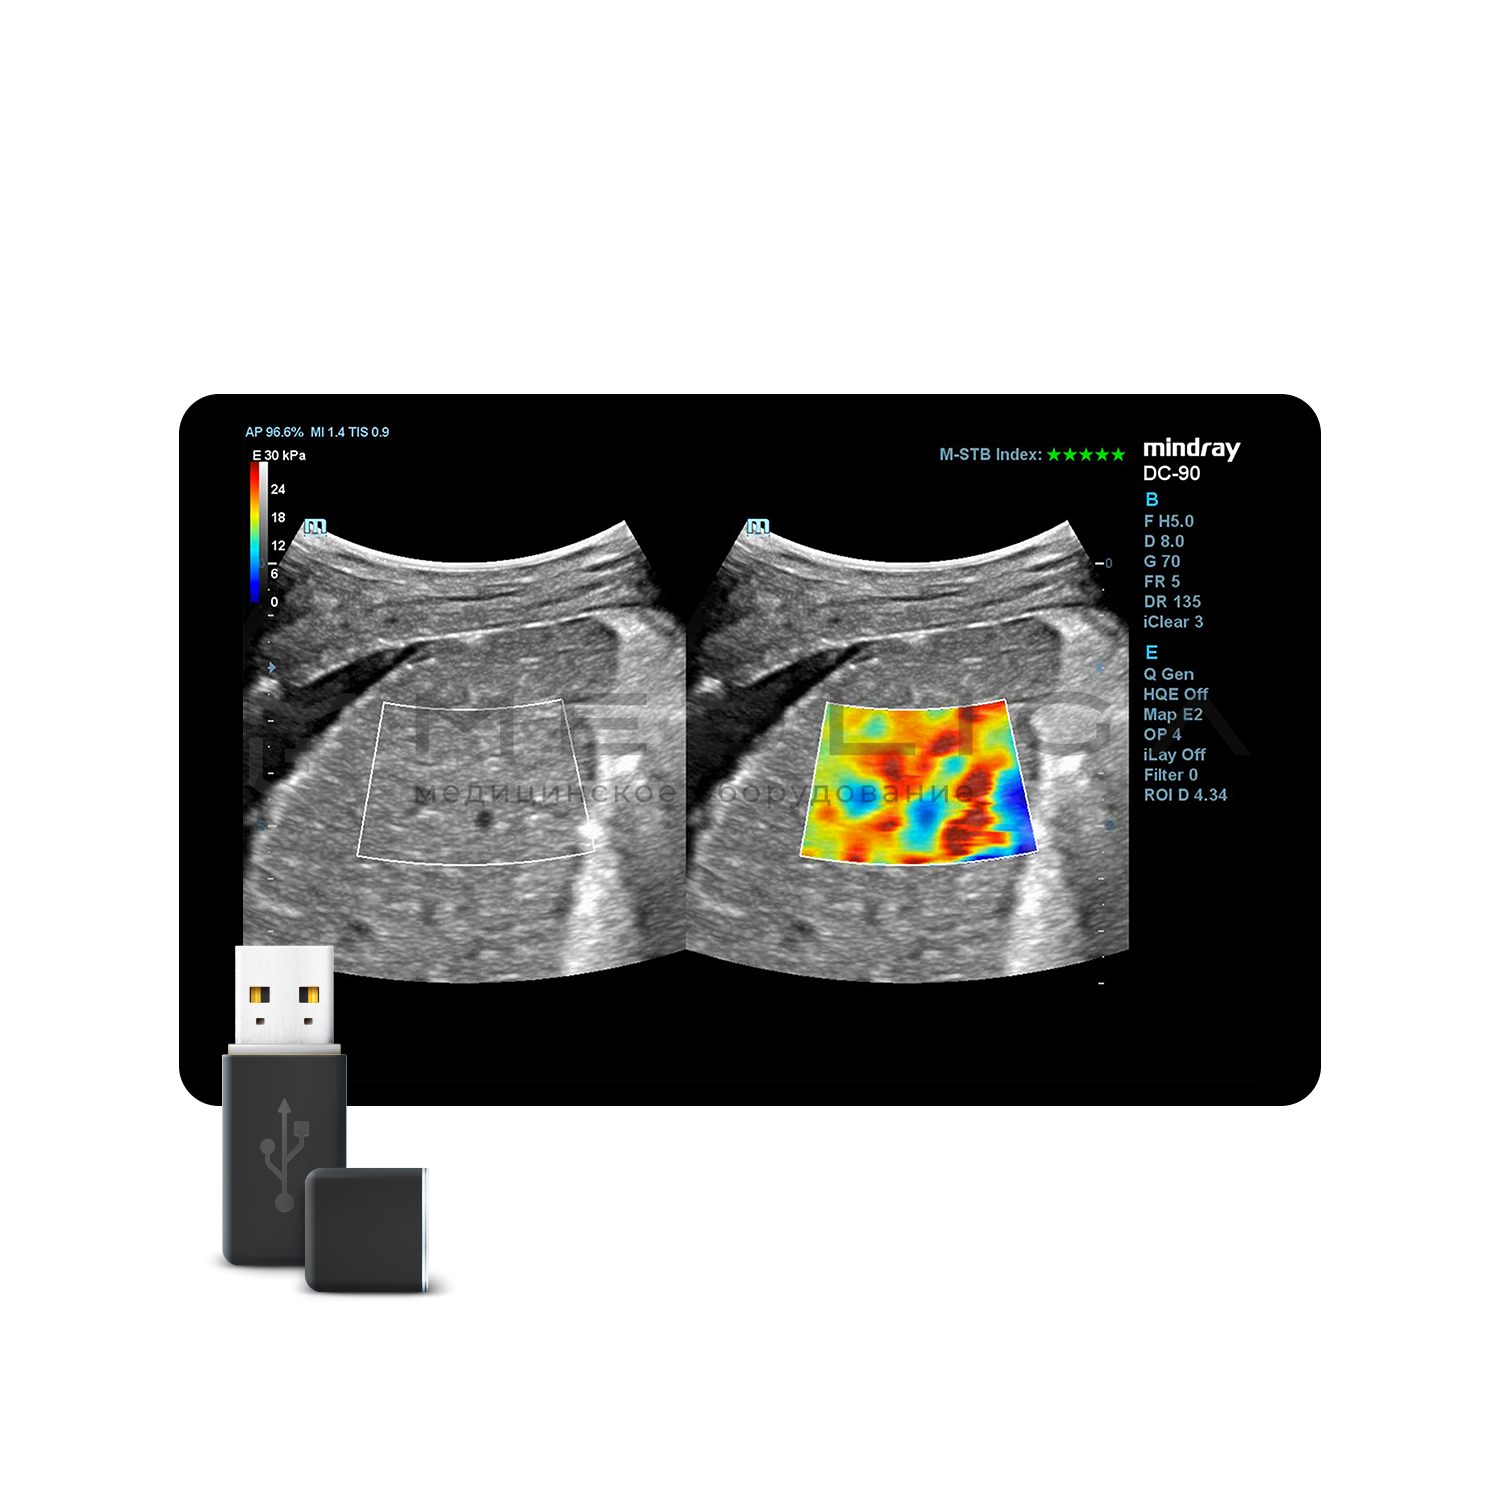

STE (Sound Touch Elastography)

STE интегрирована с эксклюзивной технологией Ultra-Wide Beam Tracking от Mindray для двумерной эластографии сдвиговой волной в реальном времени. Специализированные измерительные инструменты позволяют проводить количественный анализ модуля упругости с высокой точностью.

- на линейных датчиках

- на конвексных датчиках